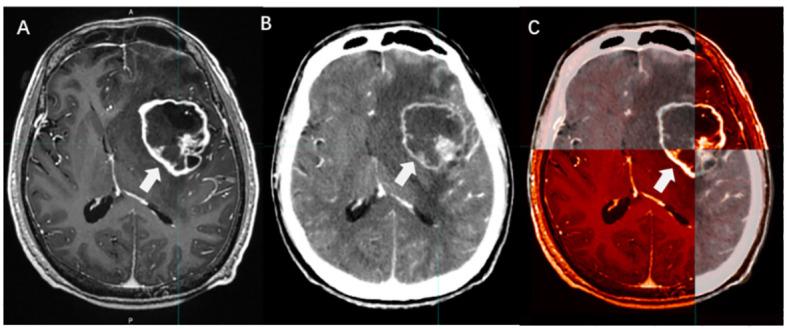

Brain metastases (BMs) are the most prevalent intracranial malignant tumors in adults and are the leading cause of mortality attributed to malignant brain diseases. Radiotherapy (RT) plays a critical role in the treatment of BMs, with local RT techniques such as stereotactic radiosurgery (SRS)/stereotactic body radiotherapy (SBRT) showing remarkable therapeutic effectiveness. The precise determination of gross tumor target volume (GTV) is crucial for ensuring the effectiveness of SRS/SBRT. Multimodal imaging techniques such as CT, MRI, and PET are extensively used for the diagnosis of BMs and GTV determination. With the development of functional imaging and artificial intelligence (AI) technology, there are more innovative ways to determine GTV for BMs, which significantly improve the accuracy and efficiency of the determination. This article provides an overview of the progress in GTV determination for RT in BMs.